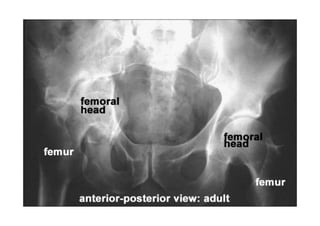

Radiologia Convencional ou Radiografia Simples ou

Raio X Simples Musculoesqauelético

• Radiografia da coluna cervical

• Radiografia da coluna torácica

• Radiografia da coluna lombar

• Radiografia de tórax

• Radiografia do ombro

• Radiografia do cotovelo

• Radiografia do antebraço

• Radiografia do punho

• Radiografia da mão

• Radiografia do abdômen

• Radiografia da bacia (pelve)

• Radiografia do quadril

Fonte: info-radiologie.ch

• Radiografia do joelho

• Radiografia do tornozelo

• Radiografia do pé